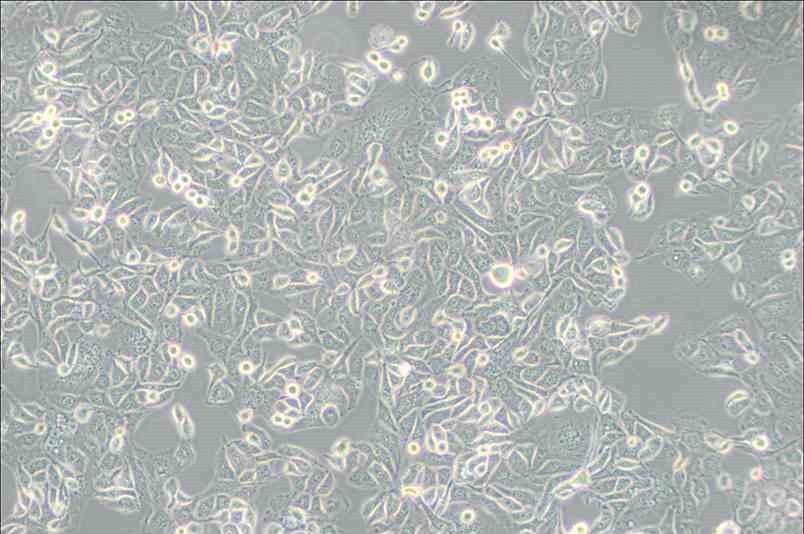

Anglne人卵巢癌細胞

細胞簡稱 :Anglne

細胞形態 :上皮細胞樣

生長特性 :貼壁細胞

Anglne細胞是由德國學者建系;A nglne細胞主要用于卵巢癌的病理學研究,抗腫瘤藥物篩選。研究證明,A nglne細胞為貼壁生長,較C OC 1細胞系培養方便。